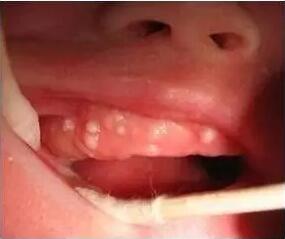

新生儿口腔内,包括牙龈、牙床或者硬颌部位,出现的白色点状小隆起,医学上称为“上皮珠”,也就是老百姓所说的马牙。

过去有“擦马牙”的习俗,老人会用毛巾裹着手指用力将马牙擦掉,实际这是很危险的,特别容易造成口腔内的感染。近年来随着医学常识的普及,很多家长已经认识到这种情况其实是正常的,过3~5个月就会自然消失,因此没有必要擦马牙。